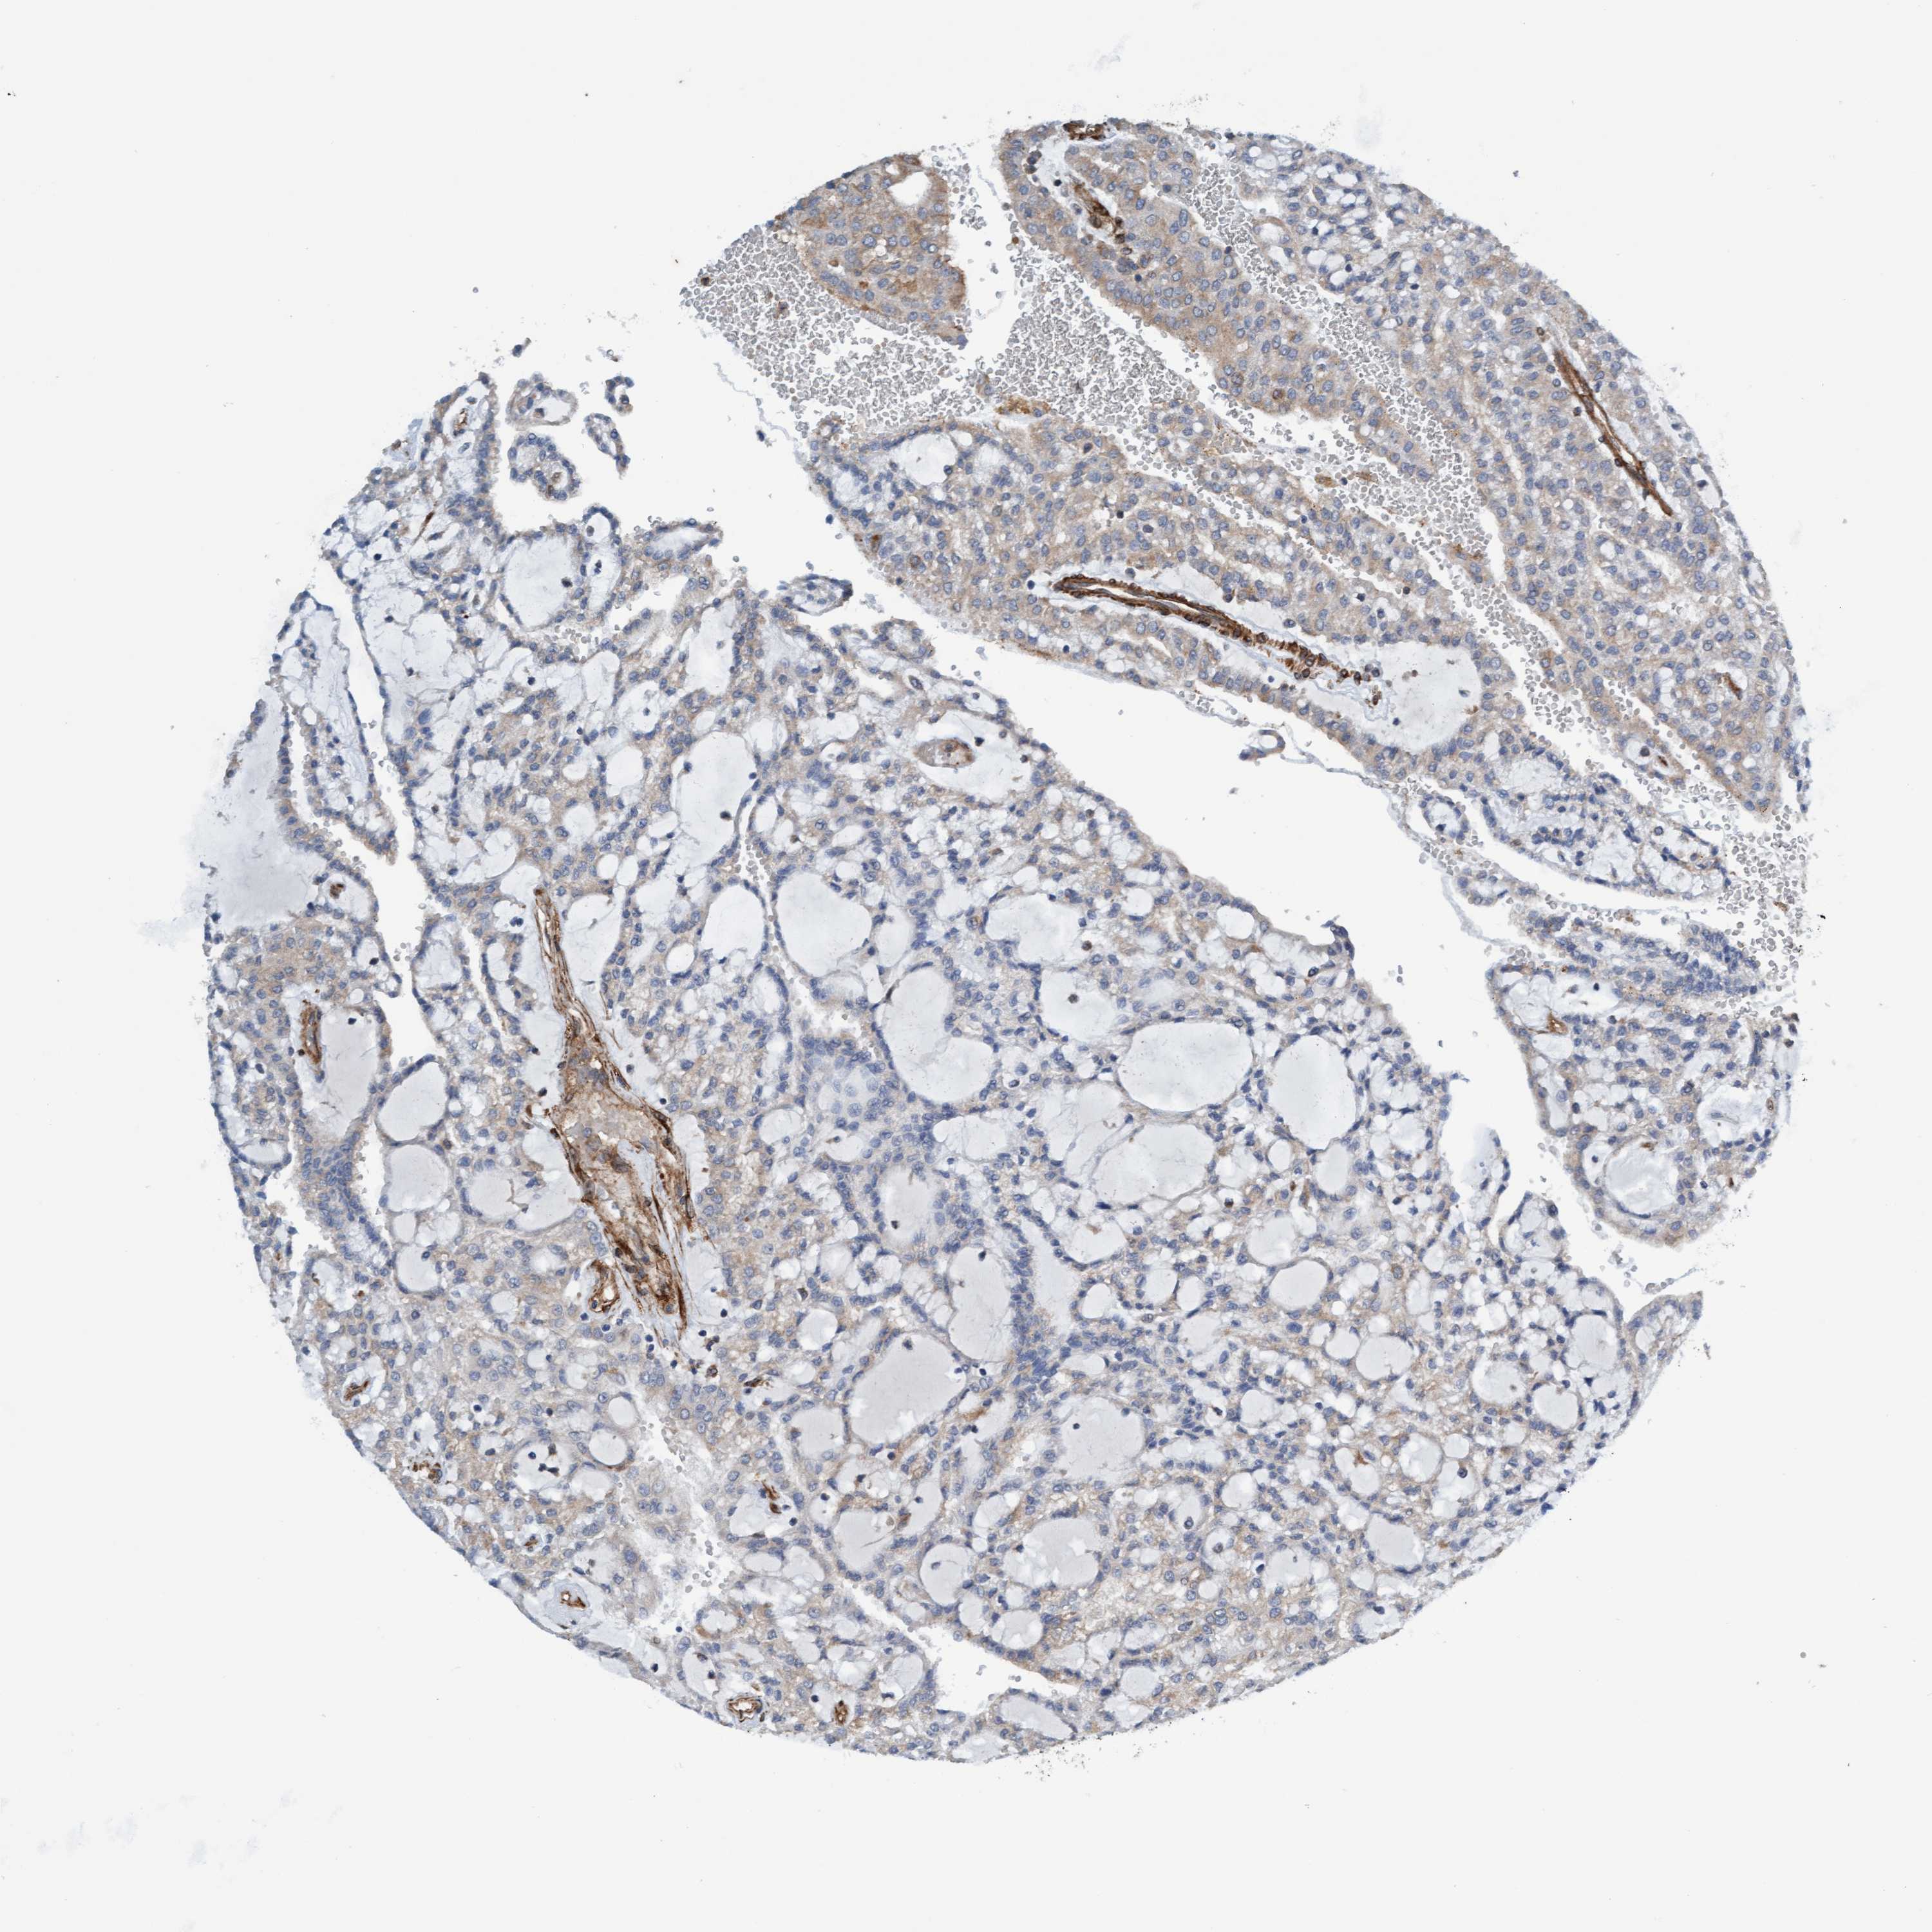

FMNL3 is validated prognostic, high expression is favorable in Kidney Renal Clear Cell Carcinoma (TCGA)

Best expression cut offi

Based on the FPKM value of each gene, patients were classified into two groups and association between prognosis (survival) and gene expression (FPKM) was examined. The best expression cut-off refers the FPKM value that yields maximal difference with regard to survival between the two groups at the lowest log-rank P-value. Best expression cut-off was selected based on survival analysis .

When clicking on this number, the vertical dashed line indicating cut-off, the interactive survival plot, and the Kaplan-Meier curve will be adjusted to show results based on the best expression cut-off.

: 9.77

TCGA RNA samplesi

RNA-seq data is reported as average FPKM (number Fragments Per Kilobase of exon per Million reads), generated by the The Cancer Genome Atlas (TCGA) .

Normal distribution across the dataset is visualized with box plots, shown as median and 25th and 75th percentiles. Points are displayed as outliers if they are above or below 1.5 times the interquartile range. FPKM values of the individual samples are presented next to the box plot.

Average pTPM 18.9

Number of samples 521